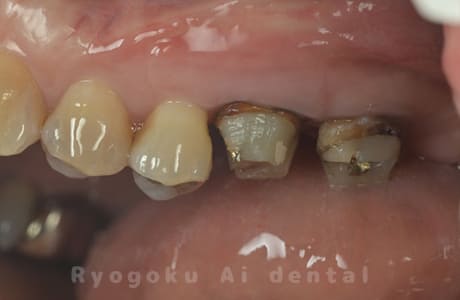

Case03

-

- 原因

- 重度縁下カリエス

- 治療期間

- 約2ヶ月(最終補綴装着まで含む)

- 治療内容

- クラウンレングスニング+歯周外科

- 治療費用

- 44,000円(最終補綴を除く)

他院で抜歯を宣告された患者様です。虫歯が歯茎の中まで及んでいたため、歯周外科・クラウンレングスニングを行い、保存を行いました。

<リスク・副作用>

手術後は痛み、腫れ、痺れ、青あざなどの副作用が生じます。痛みは痛み止めを処方しますが、腫れ、青あざは1週間程度生じる場合があります。また、部位によっては神経の走行が複雑で、痺れが残り、長期的にお薬を処方する場合があります。